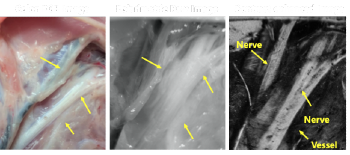

Non-Invasive, Intra‐Operative, Nerve Identification

Despite the use of visual cues, surgeons have a difficult time localizing small nerve branches with unaided eyes as they are visually indistinguishable from blood vessels or surrounding tissues. The use of electrical nerve stimulation and fluorescent dyes are helpful but their disadvantages include being invasive, distracting or toxic.

- Noninvasive and real‐time imaging

- Overcomes the risk of misidentifying nerves and reduces inadvertent trauma

- Reduces potential toxicity issues of surgical dyes

- Cost effective as it uses existing systems